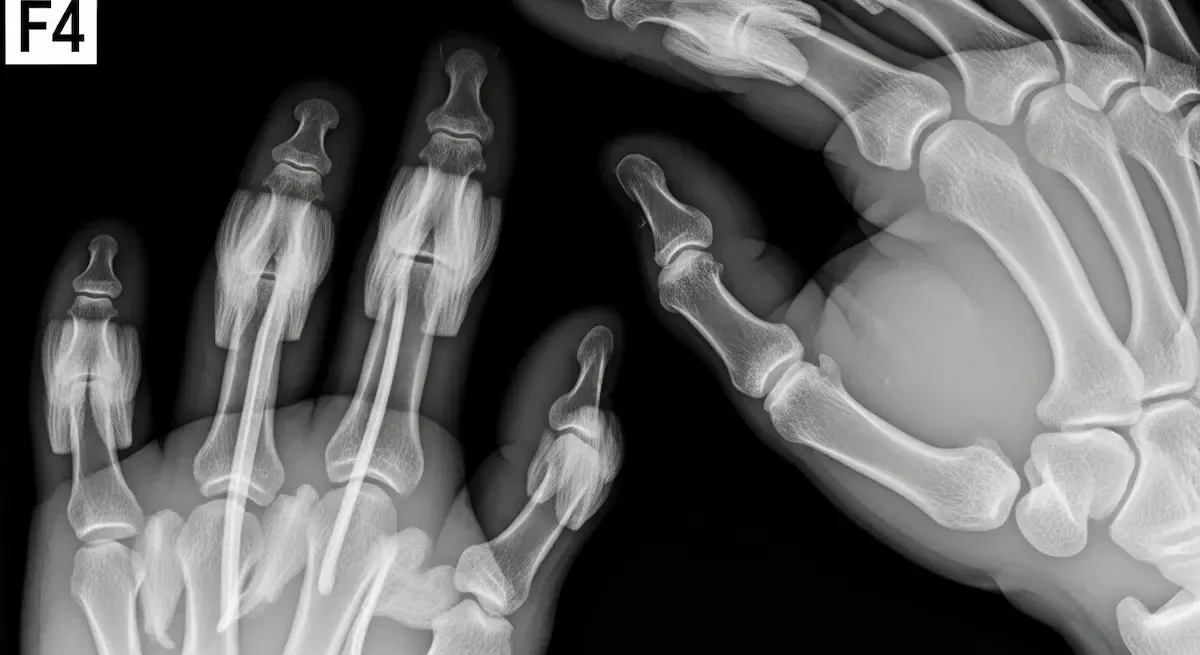

Macrodactilia: Sinais, Diagnóstico e Tratamento

Ao longo de anos dedicados à cirurgia da mão, poucos desafios se comparam à complexidade do tratamento da macrodactilia. Esta condição rara, caracterizada pelo crescimento anormal e desproporcional de um ou mais dedos, afeta aproximadamente 1 em...